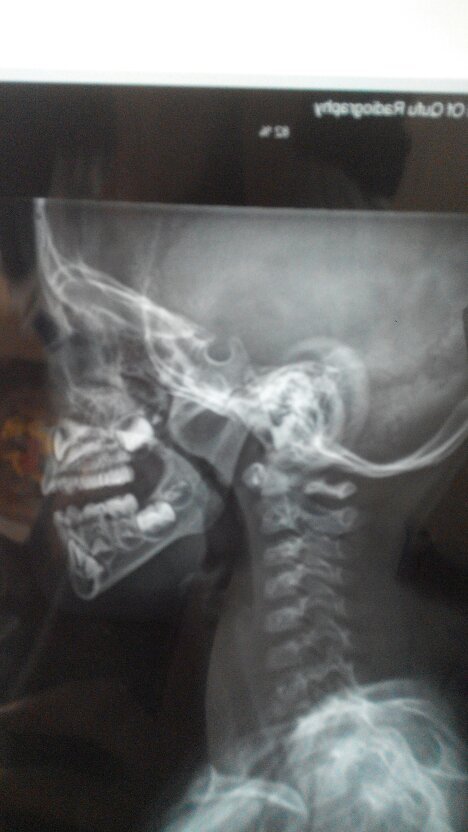

孩子平时呼吸不通畅,晚上睡眠质量不行,有事打呼噜,平躺憋气2-3秒,翻身时憋气5秒。在县医院检查医生没有给确切答复。只是说孩子太小,需要去市医院检查。检查结果上面也没有说明大小,只是拍了个片子。现在心里没底,不知道到底严重不严重。

如果是儿童,应该到大的儿童医院五官科看,拍的应该是鼻腔里面的彩色图片,不是这种片。如果这样下去对健康影响很大的。